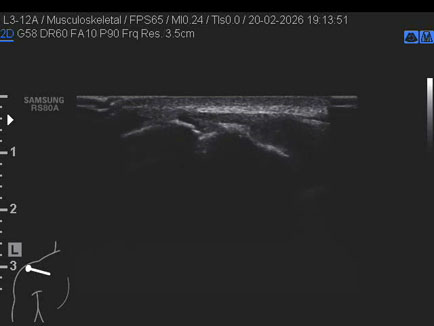

Data inserimento: 24/02/2026

Ecografia del: 20/02/2026

Strumento: Samsung

Sonda: Lineare

Età Paziente: M 20 anni

Commento all'esame: presenza di “os acromiale” (“mesoacromion”): mancata fusione di uno o più centri di ossificazione durante l’adolescenza (circa 5% della popolazione); coesiste lieve iperemia sinoviale acromion-claveare in maschio ventenne.

Conclusioni: presenza di “os acromiale” - mesoacromion (presence of “os acromiale” - mesoacromion).

Realizzazione: Dr. F. Pietro Tarini - Gubbio (PG)